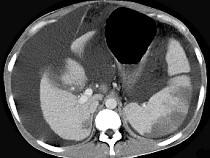

问题 患者男,29岁,乙肝病史10余年,腹胀,有移动性浊音,影像检查如图,最全面的诊断是 ( )

选项 A.肝硬化 B.肝硬化腹水 C.肝硬化腹水、脾梗、胆囊结石 D.大网膜膈下间位及脾梗 E.胆结石及脾梗

答案 C